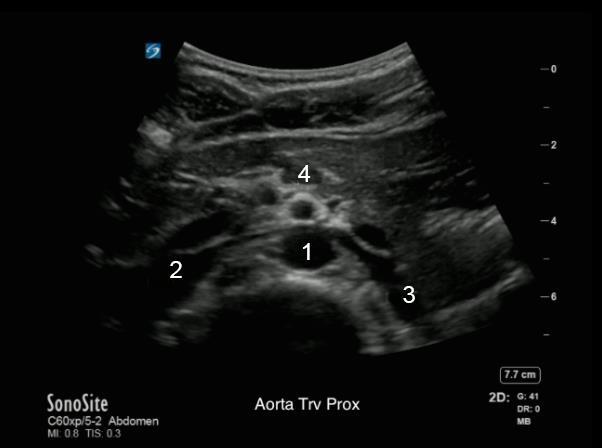

1. Aorte (Ao)

2. Veine cave inférieure (VCI)

3. Veine rénale gauche

4. Artère mésentérique supérieure